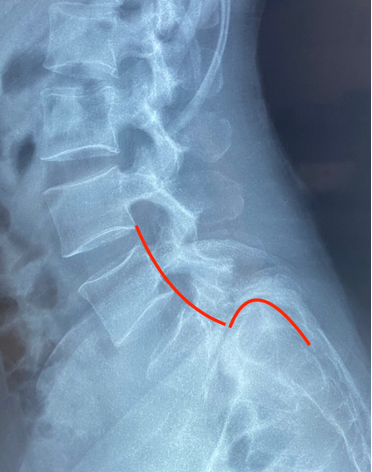

Sau khi tìm hiểu đi thăm khám kiểm tra ở nhiều nơi, chị quyết định đến khám và điều trị tại Bệnh viện Hoàn Mỹ ITO Đồng Nai. Kết quả chụp Cộng hưởng từ (MRI) và X-quang cột sống thắt lưng cho thấy chị bị trượt thân L5 ra trước độ IV - mức độ tổn thương nghiêm trọng của cột sống là mức cao nhất và nguy hiểm nhất của bệnh lý trượt cột sống. Nếu không can thiệp phẫu thuật có thể gây ra những biến chứng nghiêm trọng đến sức khỏe của người bệnh như yếu liệt hai bàn chân, thậm chí rối loạn tiểu tiện.

Đốt sống L5 trượt ra trước độ IV trên phim MRI